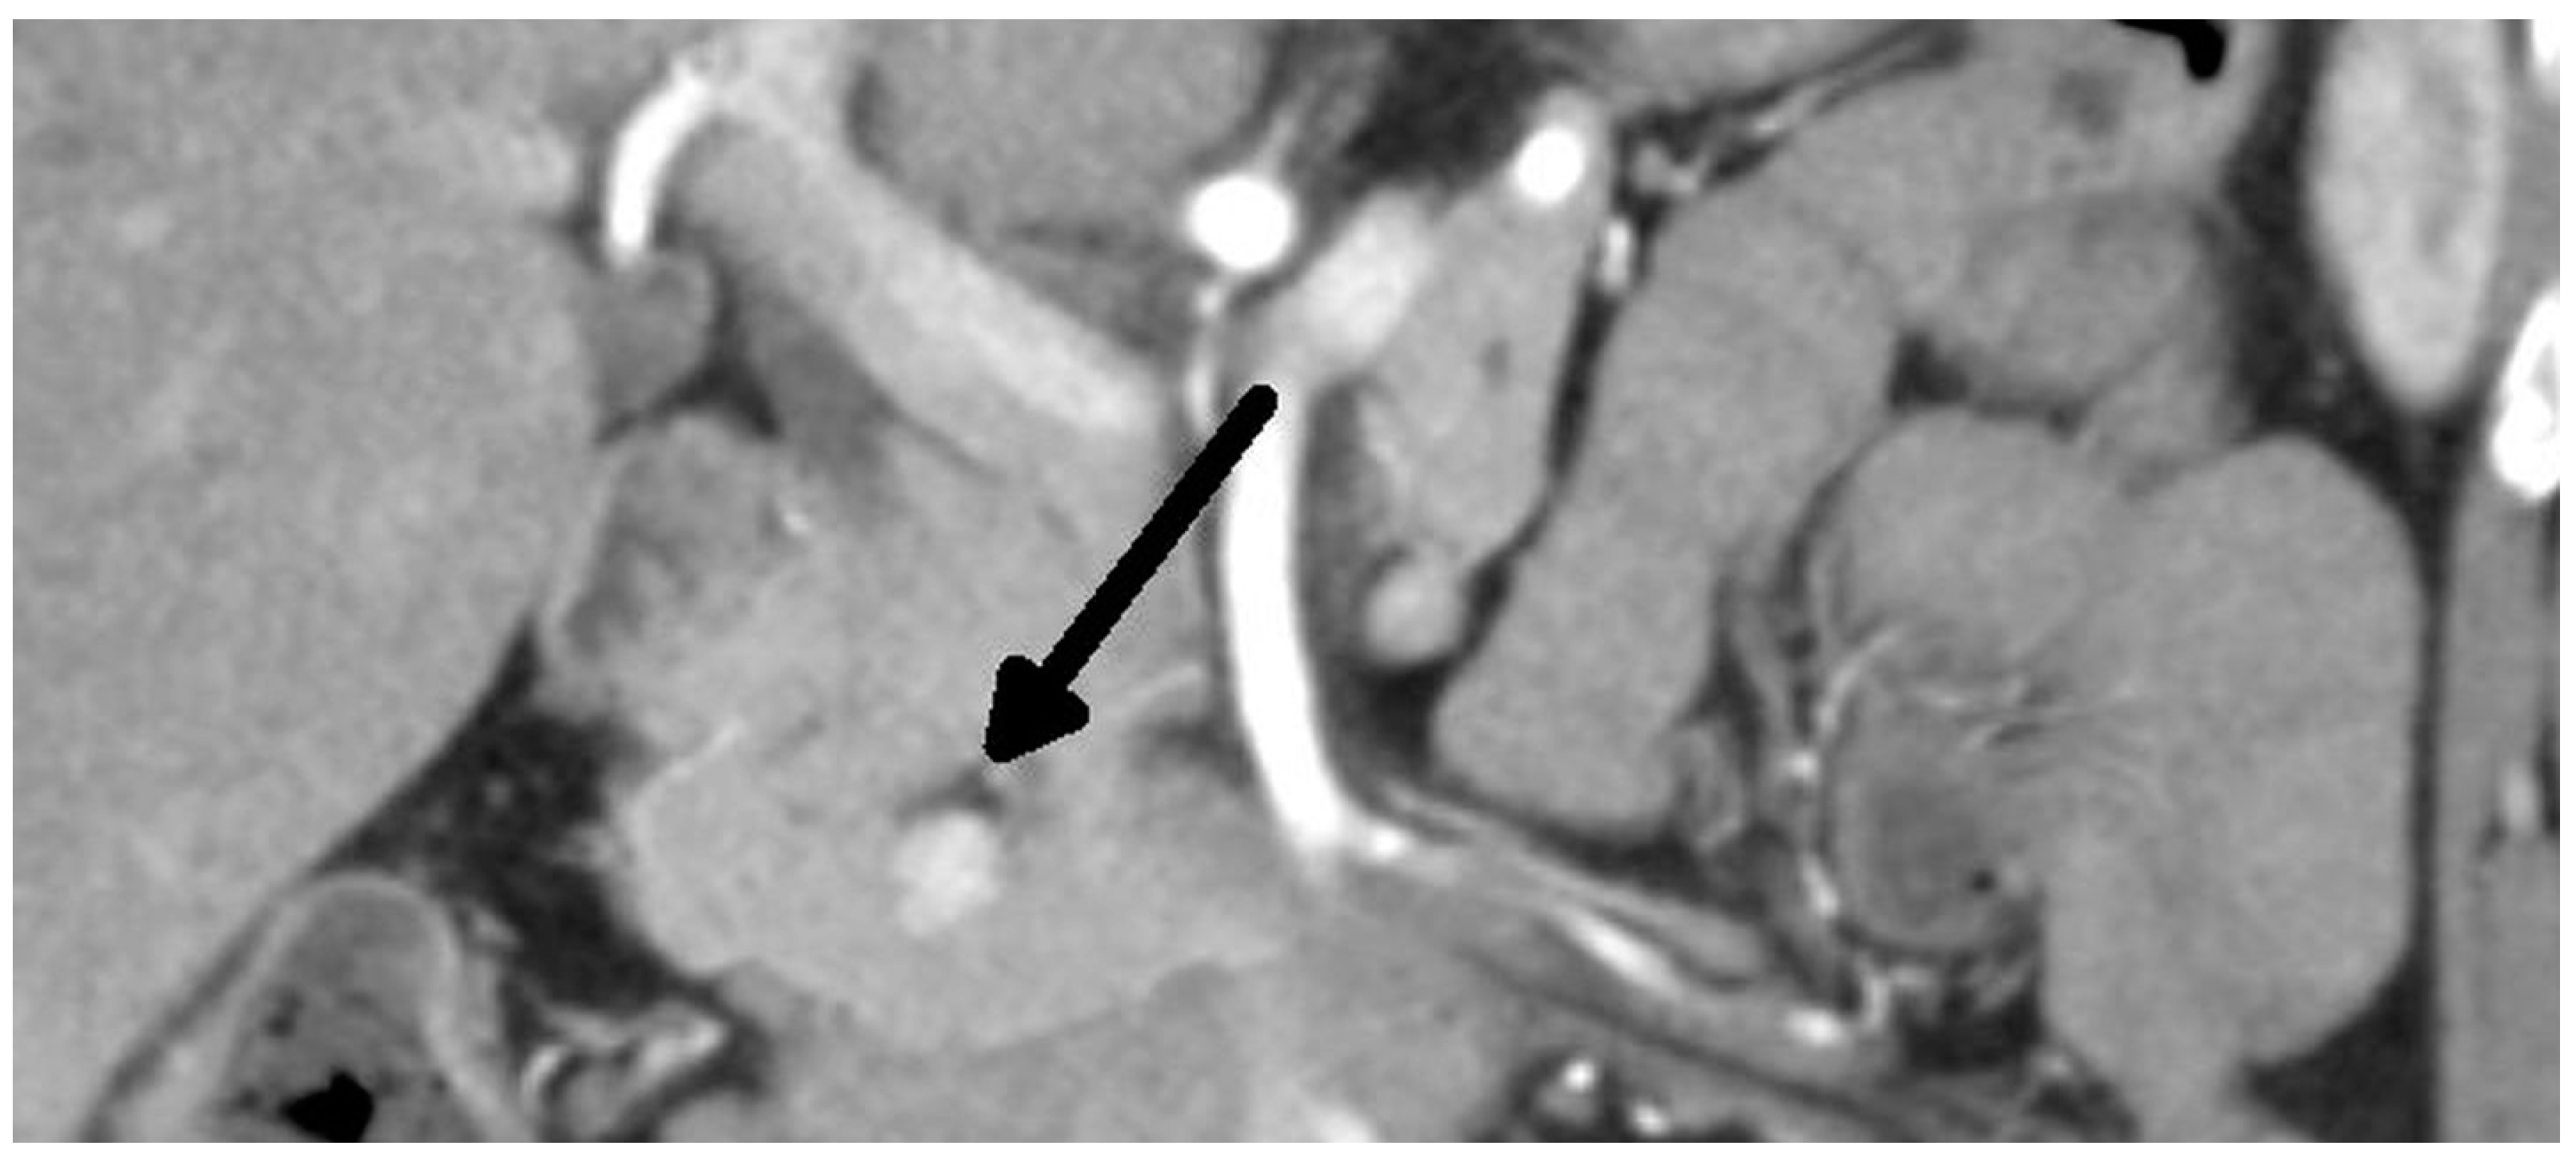

Overall, we performed a total of 116 scheduled surgeries on patients suffering from insulinoma. The surgically treated postoperative complications are listed separately. There were 79 females, with a mean age of 52 years (20–83 years, median was 51 years), and 37 males, with a mean age of 53 years (29–81 years, median was 59 years). The duration of the symptoms varied from 1 month to 25 years (mean was 3 years). All patients were examined in the 3rd Department of the Inner Medicine General University Hospital (which is focused on metabolic disease), including insulinoma localization. A fasting test was performed on all patients during hospitalization. Additionally, the levels of calcium and phosphates in the serum were examined in all patients, as well as in the hypophyseal region, to exclude MEN I syndrome. Radiological examination depends on the diagnosis period, and CT scan was used in all cases (Figure 1 and Figure 2). This was due to the unavailability of MRI, especially in the first years of the study.

Figure 1. Insulinoma—CT arterial phase (tumor marked with an arrow).